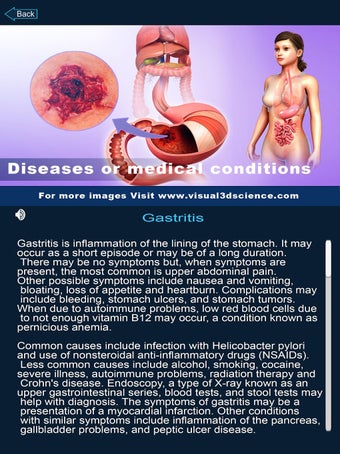

Je kunt alle informatie over de organen krijgen, inclusief hun locatie, hun functie en hoe ze eruitzien.